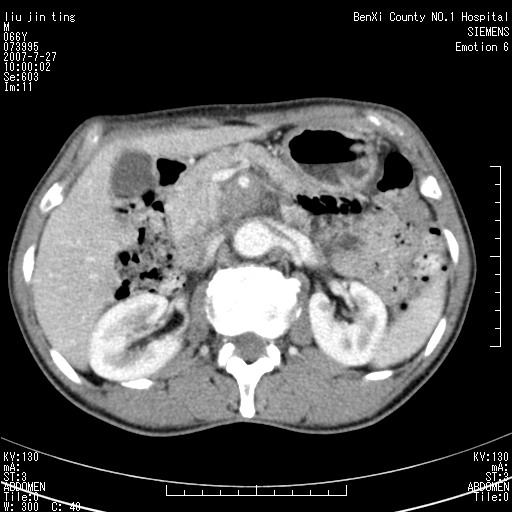

沿着肠系膜上动脉呈匍匐性生长的软组织肿块,形态不规则,包绕肠系膜上动脉,呈明显强化,考虑来源于肠系膜的恶性肿瘤

沿着肠系膜上动脉呈匍匐性生长的软组织肿块,形态不规则,包绕肠系膜上动脉,呈轻-中度强化,考虑来源于肠系膜的恶性肿瘤。

钩突是正常的,只见腹膜后淋巴结的肿大,考虑淋巴瘤或转移可能。

支持!恶性纤维组织细胞瘤可能,与淋巴瘤及淋巴结转移鉴别(腹主动脉周围清晰,其他部位亦未见明显肿大淋巴结)。

后腹膜肿块,包围血管,考虑淋巴恶性病变,淋巴瘤或转移。